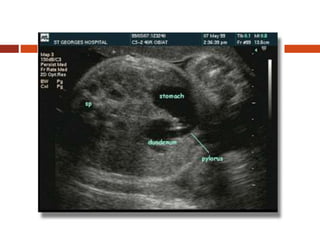

Duodenal obstruction is being

increasingly diagnosed prenatally. The

prenatal sonographic diagnosis of DO

relies on the demonstration of the “double

bubble” sign, which is due to the

simultaneous distension of the stomach

and the first portion of the duodenum. The

dilated stomach and duodenum appear

side by side across the midline of the

upper fetal abdomen

Ultrasonography (transverse view) of 24-week gestational age fetus showing

the “double bubble” sign. S—stomach, P—pylorus, D—duodenum